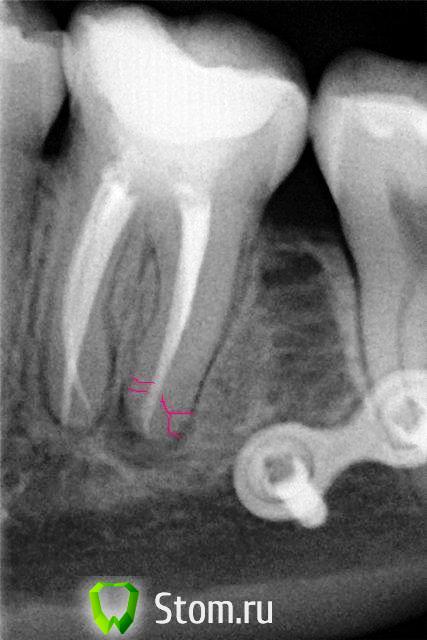

ger_berra Опубликовано 5 октября, 2011 Поделиться Опубликовано 5 октября, 2011 Как-о смущает "гомогенность корневой пломбы".Возможно гутта была плохо сконденсирована.много силера и мало филлера.Потому и получилась каша.Соглашусь с Вами по всем пунктам. Я привела в пример этот снимок,чтобы опровергнуть утверждение Ildarа,что неважно ,чем пломбировать-главное помыть.Думаю,что силер,которого,возможно,и правда было много, из апикальной части очень быстро "ушёл",апекс в дистальном достаточно широк(если совсем не раздолбан),плюс предполагается наличие дельты.Эпоксидка в этом случае дала бы лучший апикальный герметизм. ну опять же почему на медиальных все хорошо?.)) если землистая каша, то, наверное или недосушили или недозамешалиОпять,Ildarad,не соглашусь с Вами .Периодонтальная щель у медиального корня весьма расширена.И это всего лишь RVG,а не КТ. Так что вряд ли там всё хорошо.Просто повезло чуточку побольше А эндометазон,как ни замеси,всё равно со временем в ка....ку превращается. Ссылка на комментарий

ger_berra Опубликовано 1 февраля, 2012 Поделиться Опубликовано 1 февраля, 2012 Вот он,мой зубец!С кальцием в первый раз. http://s005.radikal.ru/i212/1202/8b/91723b340aa9.jpgКонтрольный снимок. http://s018.radikal.ru/i508/1202/0f/2bf181e1a446.jpg Устье одно,канал раздваивается.АН+,латералка).Ничего не болело,ну если только после первого вложения кальция,дня 4.Зуб шатался,после пломбировки окреп И 3 месяца после обтурации. http://s017.radikal.ru/i407/1202/22/0d15d14b4827.jpg Ссылка на комментарий

Kivilgar Опубликовано 1 февраля, 2012 Поделиться Опубликовано 1 февраля, 2012 (изменено) Вот он,мой зубец! Не могу удержаться, чтоб не показать свой скверный характер: щель по видимому осталась, не плотно уложили пломбировочный? http://s018.radikal.ru/i503/1202/f0/5af086e54f81.jpg Все равно очень нравится работа. Изменено 1 февраля, 2012 пользователем Kivilgar Ссылка на комментарий

SanyaDok Опубликовано 3 февраля, 2012 Поделиться Опубликовано 3 февраля, 2012 (изменено) Снимка,к сожалению,нет.Эти фотки просто попались под руку(что было...)По памяти где-то до №40,но форма каналлов не идеально круглая,а произв.формы(дистальный щелевидний по-моему)по-этому много щифтов и пошло,В принципе можно сравнить с последним фото (21,11) там пошло много штифтов.Ну,приблизительно так_в каналле разработанном последним файлом №40 ляжет еще 3-4 №30.Короче,дело случая-сколько можно уплотнить_уплотняю,штифты особо не считаю.Я не большой спец-делаю,как мне кажется,правильно...Вот нашел еще один подобный снимок(это не окончательный снимок-медиальные к/к еще допломбировывались.Пометки со снимка убрать не могу)-когда легло много штифтов.Опять-же-фото изначально с телефона,качество плохое. Изменено 3 февраля, 2012 пользователем SanyaDok Ссылка на комментарий